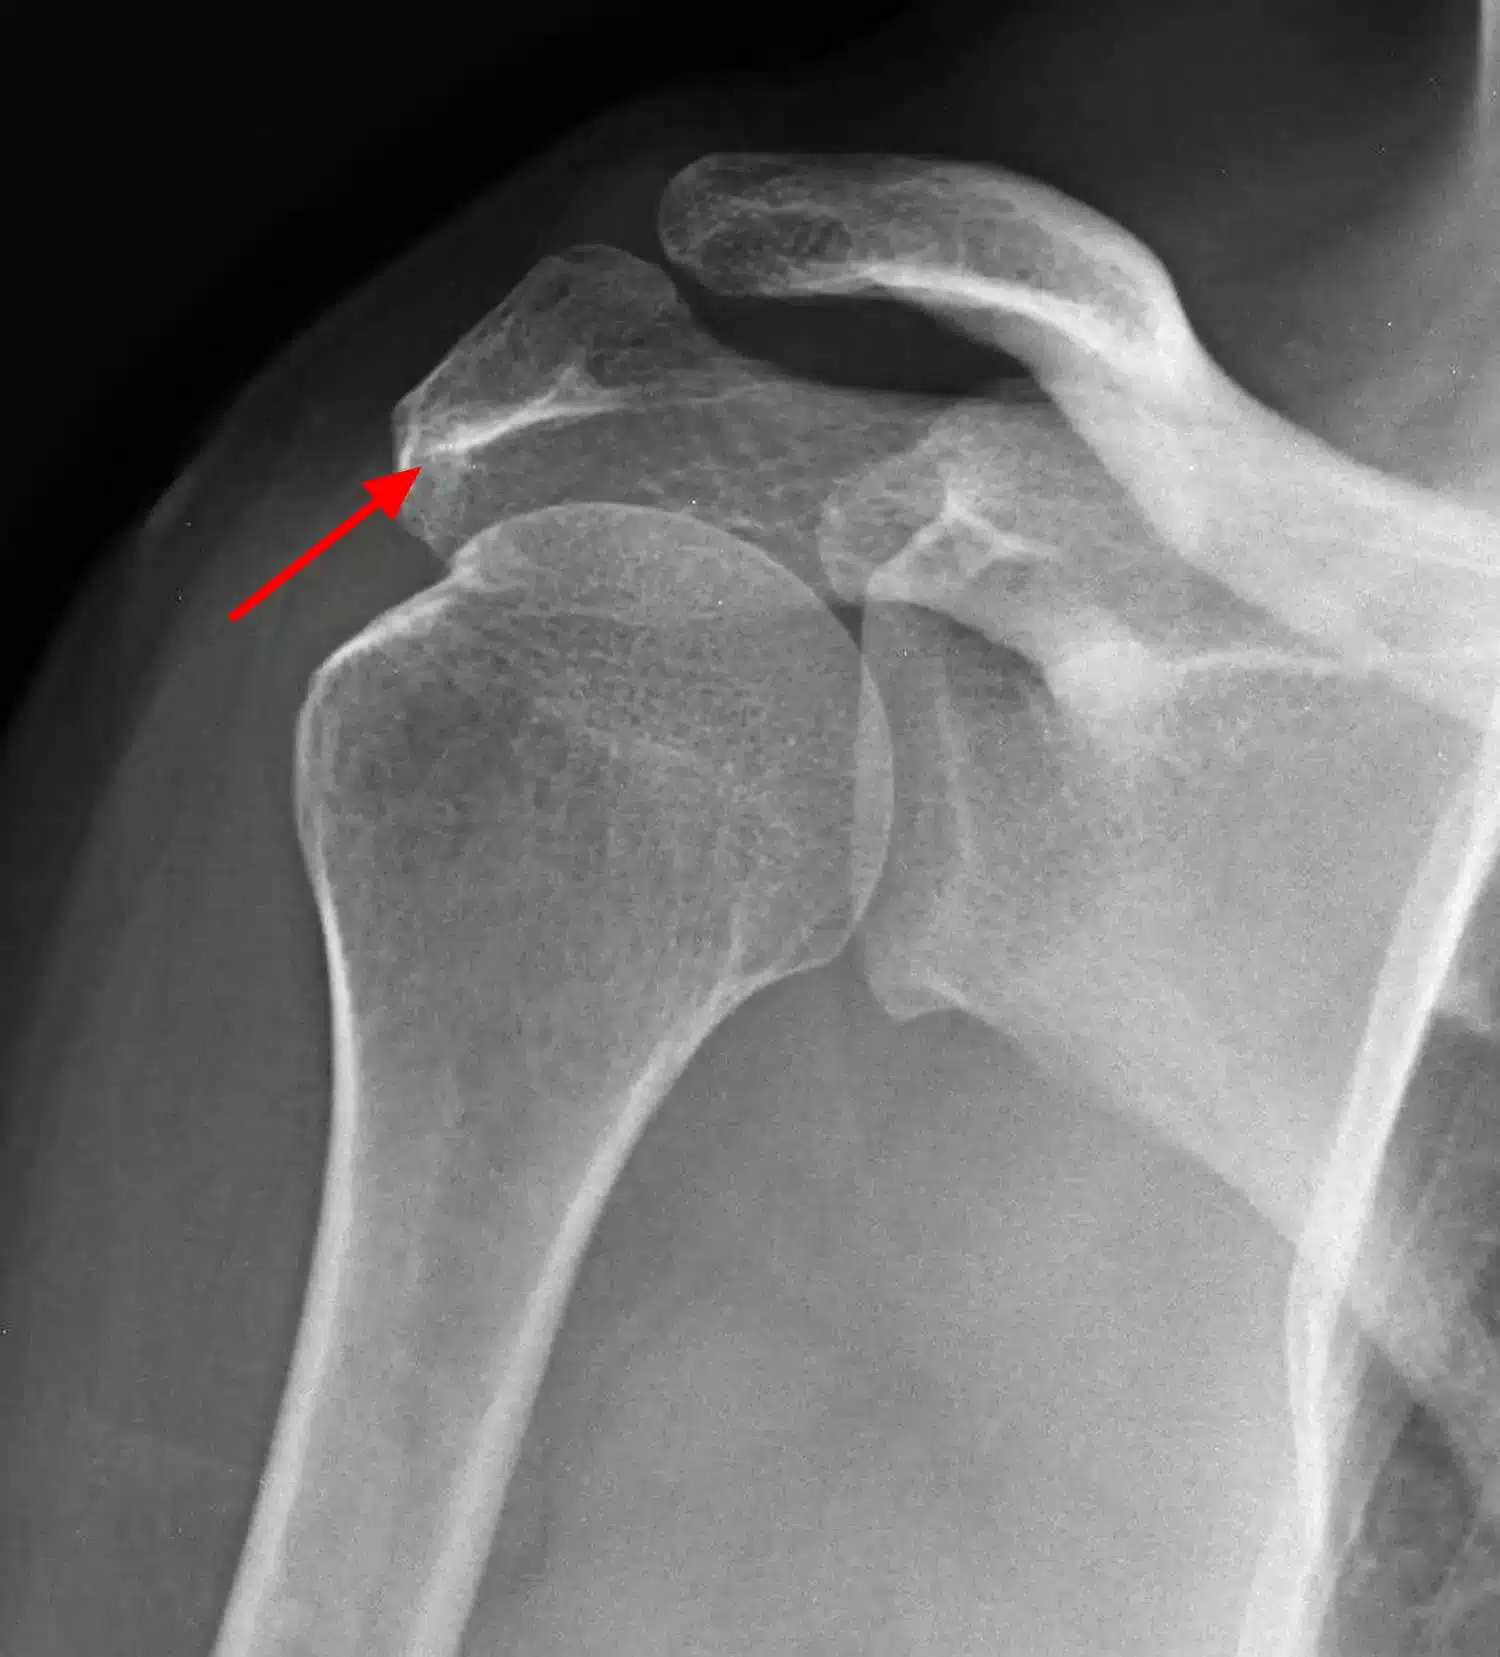

پارگی تاندون روتاتور کاف (Rotator cuff) | علائم، دلایل، روشهای درمان و فیزیوتراپی تخصصی در سال1405 ادامه مطلب »

همهچیز درباره عمل پارگی تاندون شانه در سال 1405 | مراحل جراحی، نکات طلایی و مراقبتهای بعد از عمل ادامه مطلب »

جراحی مفصل شانه در سال 1405 | قیمت، نکات طلایی و راهنمای قدمبهقدم برای بازگشت بدون درد ادامه مطلب »